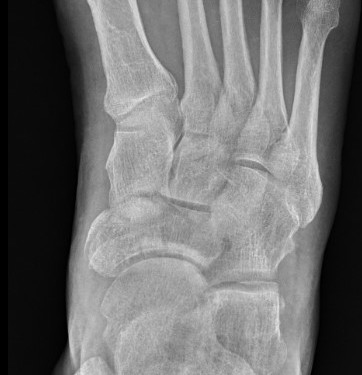

Imaging

Acute displaced navicular fracture